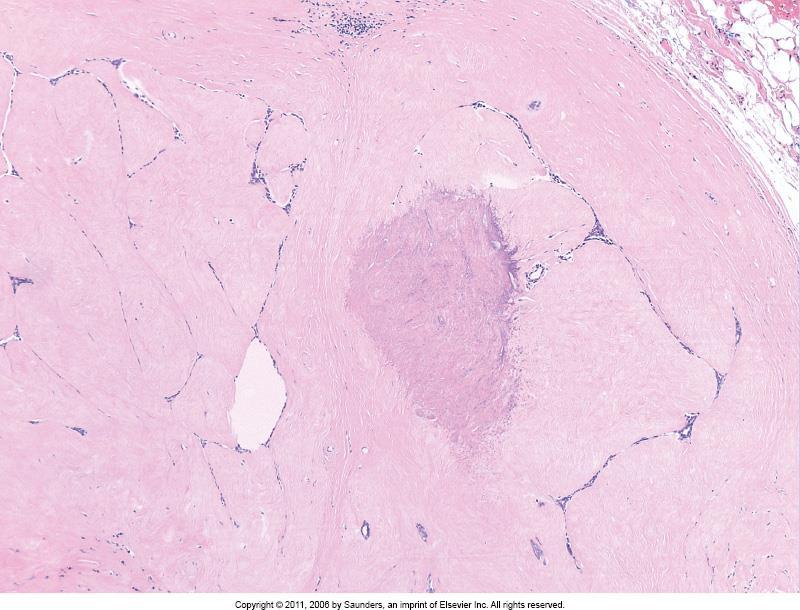

5-14% of breast carcinomas High incidence of multifocal and bilateral disease Tumour cells may show mucin filled vacuoles E-cadherin negative

E-cadherin

Central fibroelastosis Entrapped benign ducts Associated epithelial hyperplasia <1cm radial scar >1cm complex sclerosing lesion Increased risk for subsequent breast cancer development